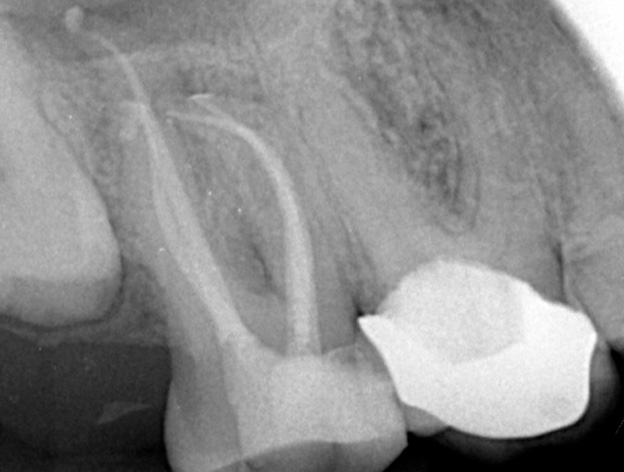

The purpose of the root canal procedure is to remove the inflamed tissue or bacteria inside the root canal and thus allow the supporting tissues to heal. After cleaning the root canal system, the space created is filled with a root filling, using a rubber material called gutta-percha.

Step 2: Cleaning the Root Canal System Our dentist carefully cleans and shapes the root canal system to remove all inflamed tissue and bacteria. The time required depends on the complexity and number of canals in the tooth root.

Step 3: Filling and Sealing Once cleaned, the root canal system is filled with a root filling, typically using a rubber material called gutta-percha. For cases with long-standing infection, anti-bacterial medicaments may be placed inside the canals between visits to kill any remaining bacteria, sealed by a temporary filling for about one week.